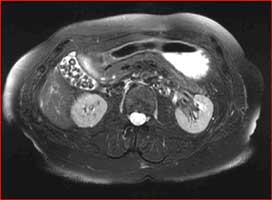

Abdominal MRI with numerous gallstones